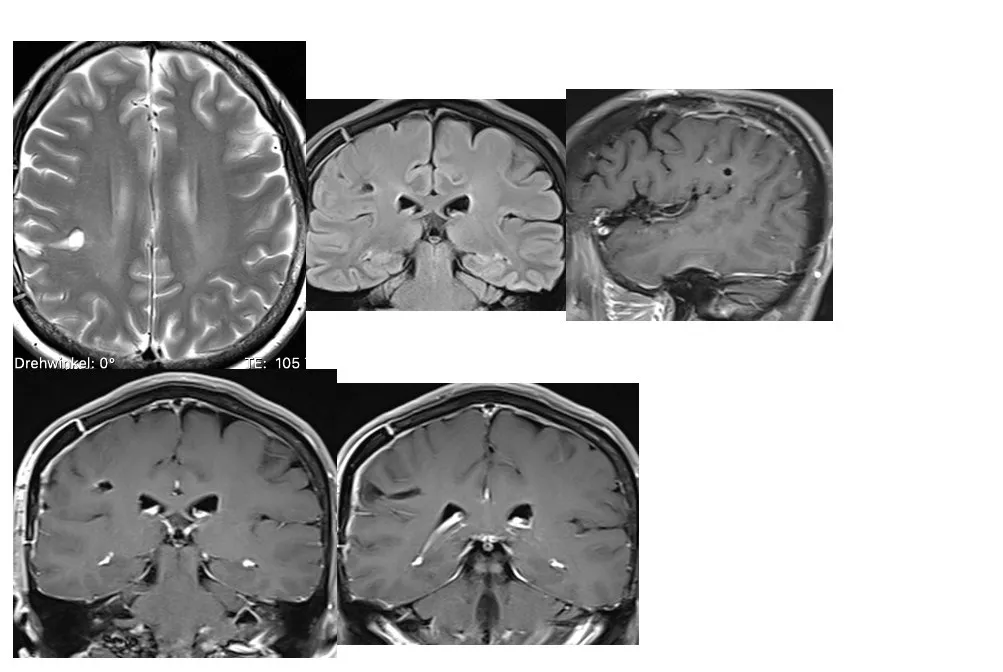

肿瘤全切了吗?术后是否复发?

复查MRI对比,右额后中央深层海绵状瘤完全切除,效果满意!

影像显示海绵状血管瘤被完全切除,没有任何不良副作用。代我向病人送上我的祝福,她应该充分放松,目前她(的恢复状况)一切良好。